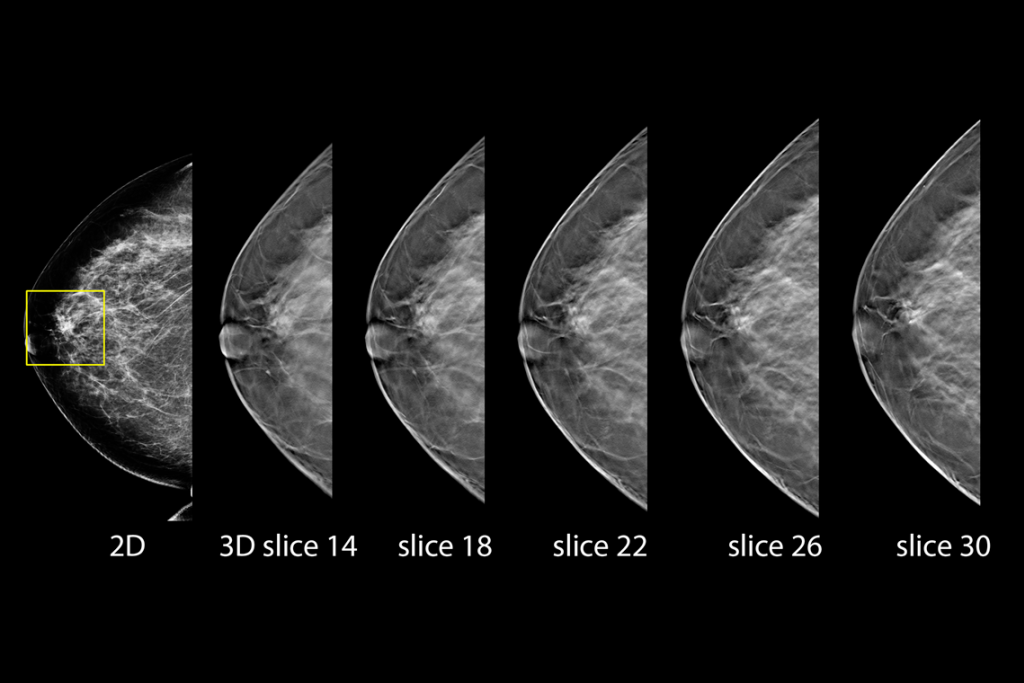

The Selenia Dimensions system delivers proven accuracy of our 3D Mammography exam to detect significantly more invasive breast cancers earlier and reduce call backs vs 2D alone.2-6,*

Detects up to 65% more invasive breast cancer, and reduces recalls by up to 40%, compared to 2D alone.2-4,*

Superior Accuracy

Superior accuracy for women with dense breasts compared to 2D alone.6

Clinical Images